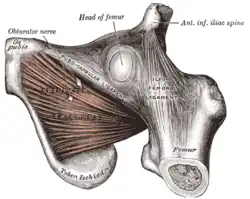

Left levator ani from within. The obturator externus.

The obturator externus. Left hip-joint, opened by removing the floor of the acetabulum from within the pelvis.